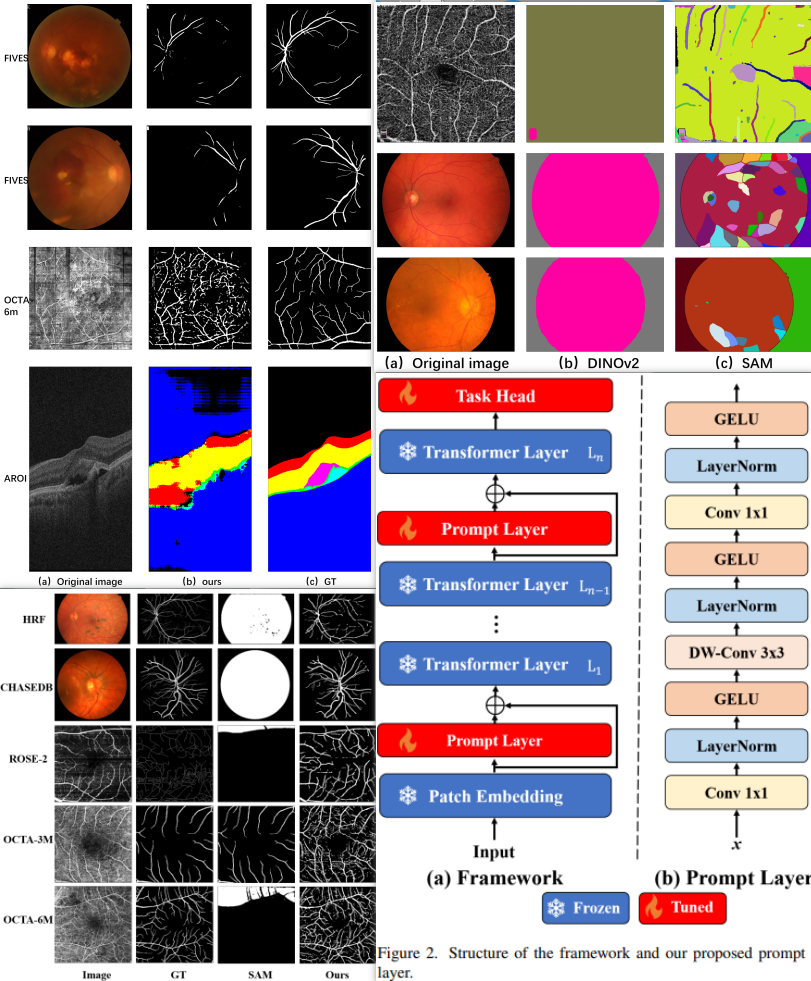

- Adapting Through Adapters

Learnable Ophthalmology SAM

在眼科的多目标分割:通过学习新的可学习的提示层对SAM进行了一次微调,从而准确地分割不同的模态图像中的血管或病变或视网膜层。